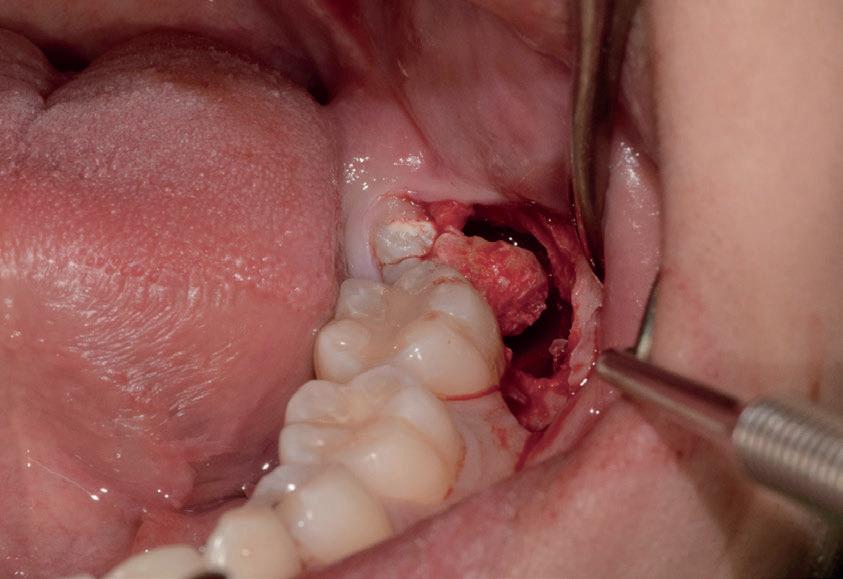

Il seguente caso chirurgico è di un 4.8 mesio-inclinato e parzialmente incluso. Dopo un’incisione a busta, il

dente è stato separato al centro per fare una coronectomia, prima della porzione distale e successivamente della porzione mesiale. Facendo leva quindi è stato possibile rimuovere le radici unite. Figg. 165-172

Figg. 165-172 - Caso 3: tecnica di estrazione con divisione orizzontale utilizzando il manipolo dritto. Fig. 165 Fig. 166 Fig. 167 Fig. 168 Fig. 169 Fig. 170 Fig. 171 Fig. 172